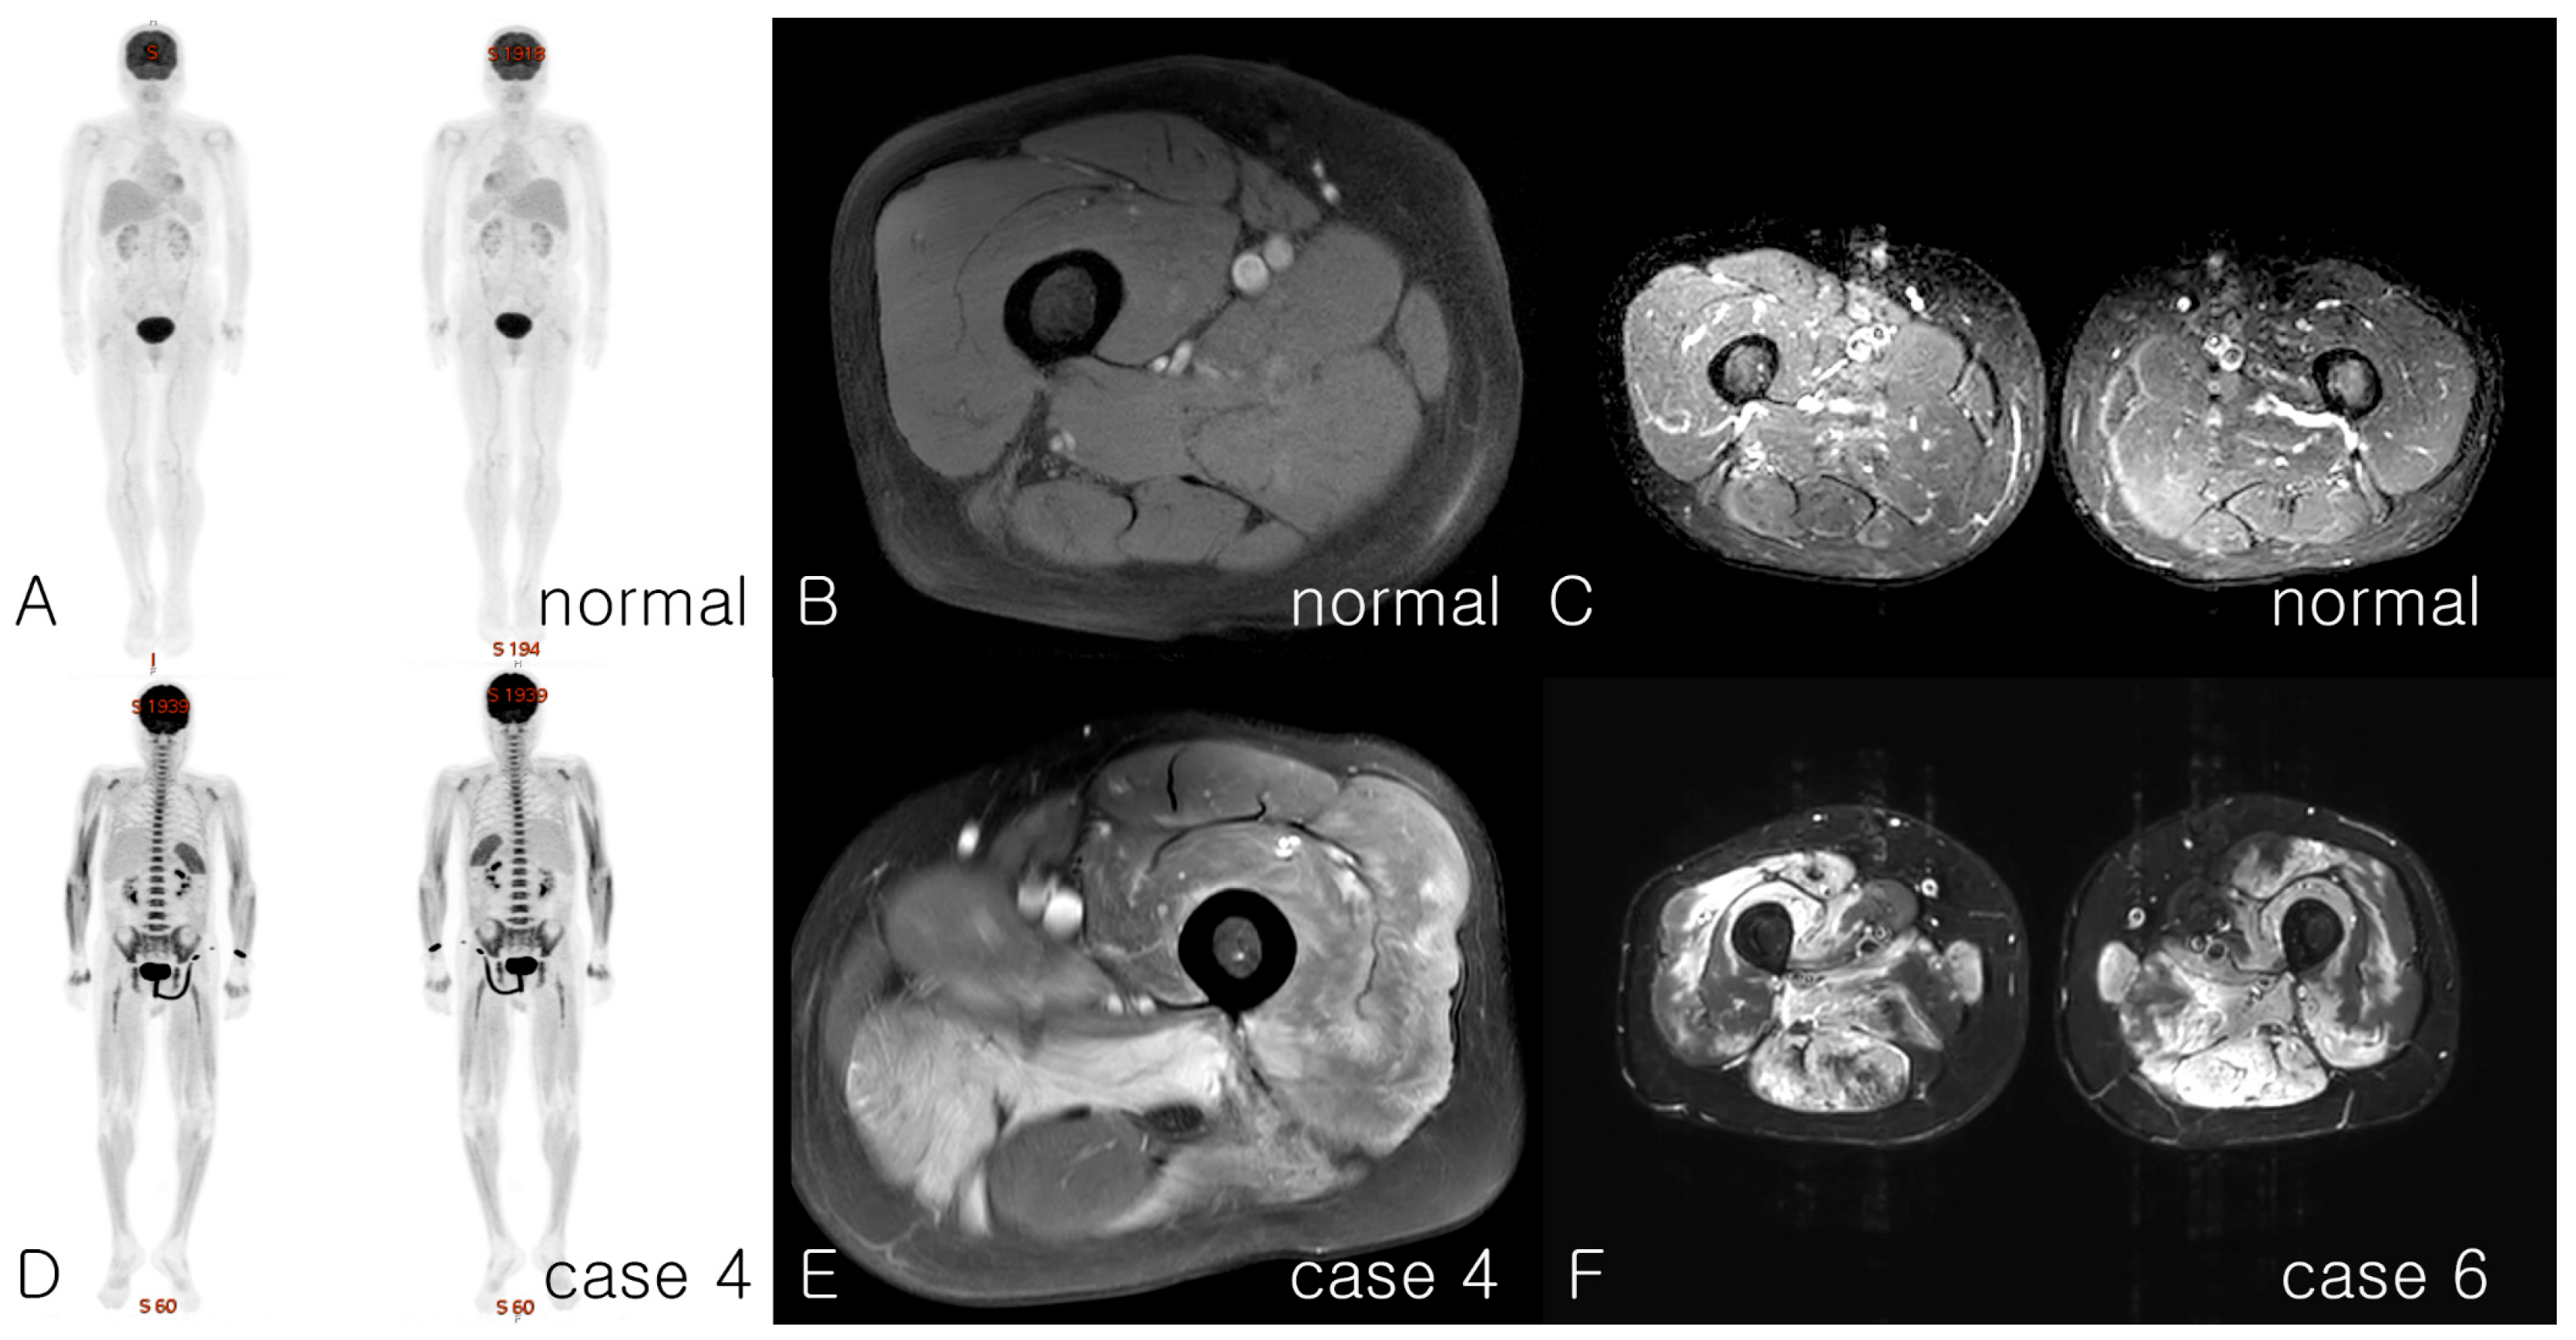

| MRI, involved muscles | Whole-body muscle: proximal and distal, upper and lower limbs | Only shoulder MRI checked: Proximal Arm, chest, back, neck | Whole-body muscle: proximal and distal, arm, leg, back | Diffuse upper and lower limbs | Proximal upper and lower | Proximal, upper and lower limbs, back | Whole-body muscle: proximal and distal, upper and lower limbs, back and chest | Proximal, upper and lower limbs, back | Whole-body muscle | Subtle myopathic change, upper and lower limbs | |